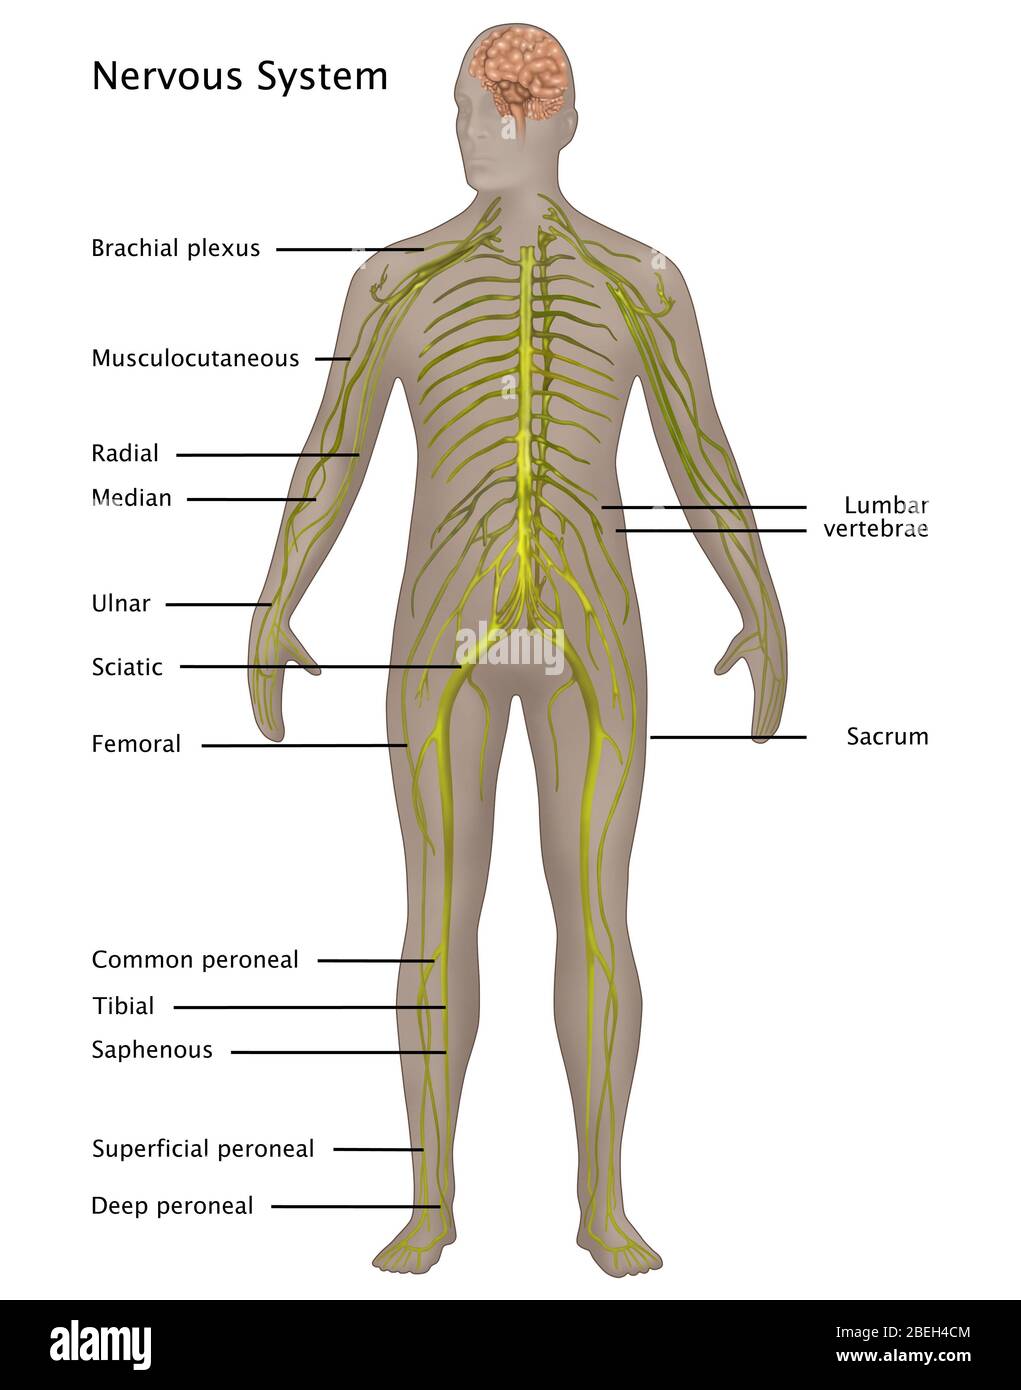

RFPAYTH0–Innere Organe, männlichen Körper - schematische Darstellung der menschlichen Anatomie Illustration - auf weißem Hintergrund.